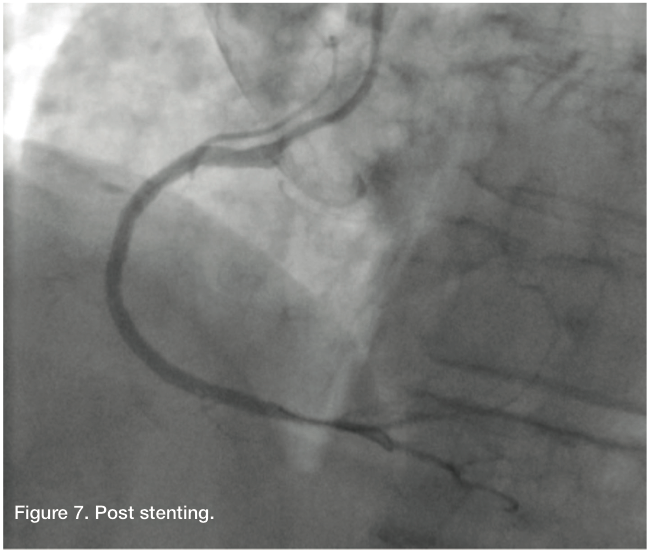

The patient’s angiographic finding demonstrated a degree of patency, a result of the previous retrograde balloon dilation of the RCA. We changed to an Amplatz right (AR) Mod guide catheter, because the AL 0.75 was engaging the dissection too deeply and would not allow us to steer our wire in the desired direction. Using a Fielder wire and a 1.25 mm balloon, we were able to cross, and advance the balloon and wire distally into the PDA and exchange out for an Iron Man support wire (Abbott Vascular). After removal of the 1.25 balloon (Medtronic), we predilated with a 2.0 x 15 Apex catheter (Boston Scientific). This was then followed by a 2.5 x 15mm AngioSculpt (Angioscore) to predilate the mid and distal RCA. Intravascular ultrasound (IVUS) (Volcano) showed that the vessel was actually about 3.0 mm in the distal and mid portion, with a dissection clearly noted in the proximal portion. The vessel was about 4.0 mm proximally. We took a 3.0 x 30 mm Resolute (Medtronic) drug-eluting stent and deployed it from the distal to mid RCA. The Resolute was overlapped with another 3.0 x 30 mm Resolute, and then a 3.5 x 26 mm Resolute, going all the way back to the proximal RCA, but not involving the ostium. All stents were post dilated with Quantum balloons at high pressure. Stent size and apposition was confirmed by IVUS. Final angiography revealed TIMI-3 flow without dissection, perforation, or embolization. The patient had an uncomplicated hospital course and was discharged home the next morning.